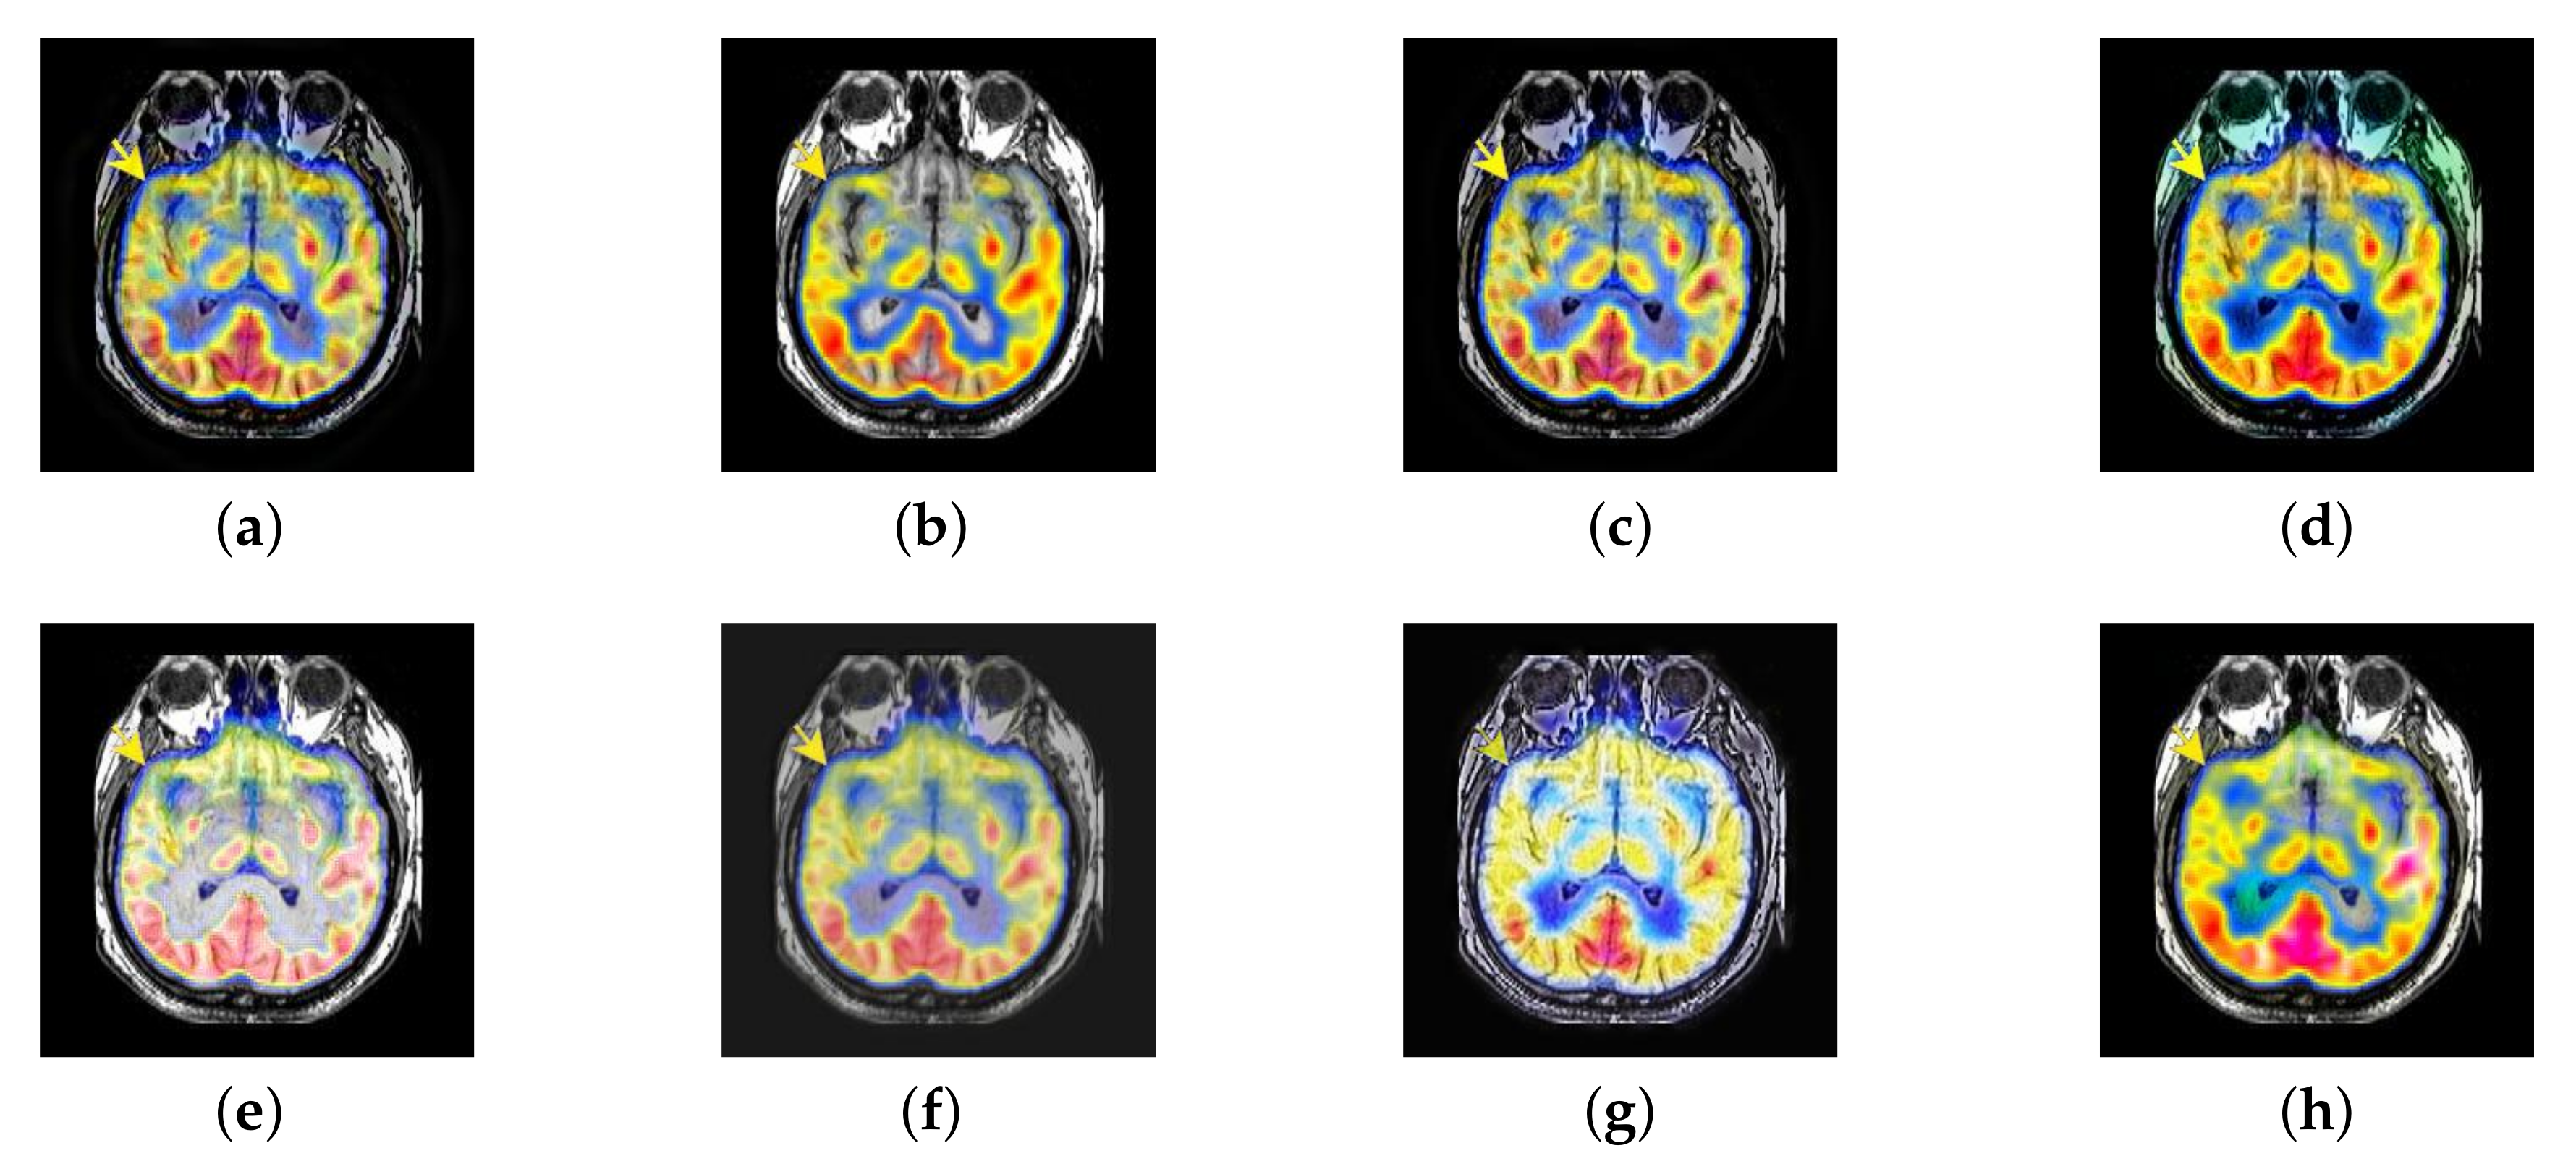

4.4. The Fusion of MRI-CBF

Cerebral blood flow diagram (CBF), which indicates the amount of blood flow in brain tissue with color. Red, yellow, green, blue, and black successively indicate the amount of blood flow from more to less. It is mainly used to detect the blood flow supply condition, elasticity, tension, and peripheral resistance. However, with the development of medical science, CBF image is often inferior in the diagnosis of brain diseases due to its lack of structural information. Therefore, MRI which is good at expressing structural information, is introduced to fuse in the current trend of brain medicine.

In this section, there are four image sets to fuse, each containing a MRI image and its corresponding CBF image in Figure 41. In Figure 42, Figure 43, Figure 44 and Figure 45, it can be seen that the structural information of fusion images obtained by our algorithm is complete. The color is not distorted, and the spectral features are natural. The fusion image based on DTCWT and NSCT algorithm have high color fidelity but less structural information. Other algorithms, such as IGM, LPSR, and FusionCNN, only focus on the structural information of the MRI image and ignore the color information of the fused image. Although the image structure information obtained by DDcGAN fusion algorithm is relatively complete, the edge of color information is not clear, which has a great influence on image contrast.

Figure 42.

Fused medical images obtained by different algorithms (Figure 41a,b): (a) DTCWT, (b) GFF, (c) NSCT, (d) LPSR, (e) IGM, (f) FusionCNN, (g) DDcGAN, and (h) FusionNet.

Figure 43.

Fused medical images obtained by different algorithms (Figure 41c,d): (a) DTCWT, (b) GFF, (c) NSCT, (d) LPSR, (e) IGM, (f) FusionCNN, (g) DDcGAN, and (h) FusionNet.

Figure 44.

Fused medical images obtained by different algorithms (Figure 41e,f): (a) DTCWT, (b) GFF, (c) NSCT, (d) LPSR, (e) IGM, (f) FusionCNN, (g) DDcGAN, and (h) FusionNet.

Figure 45.

Fused medical images obtained by different algorithms (Figure 41g,h): (a) DTCWT, (b) GFF, (c) NSCT, (d) LPSR, (e) IGM, (f) FusionCNN, (g) DDcGAN, and (h) FusionNet.

The averaged subjective scores of MRI-CBF fusion images obtained by the above methods are shown from Figure 46 and Figure 47. Our fusion algorithm has obvious advantages in EN, FMI, SSIM, , , and AG from Figure 48, Figure 49, Figure 50, Figure 51, Figure 52, Figure 53, Figure 54, Figure 55, Figure 56 and Figure 57. Other metrics are inferior to those of FusionCNN, GFF, and LPSR fusion algorithm. However, as we have mentioned before, there may be inconsistency between subjective indicators and objective indicators, but this does not affect the assessment of image quality.